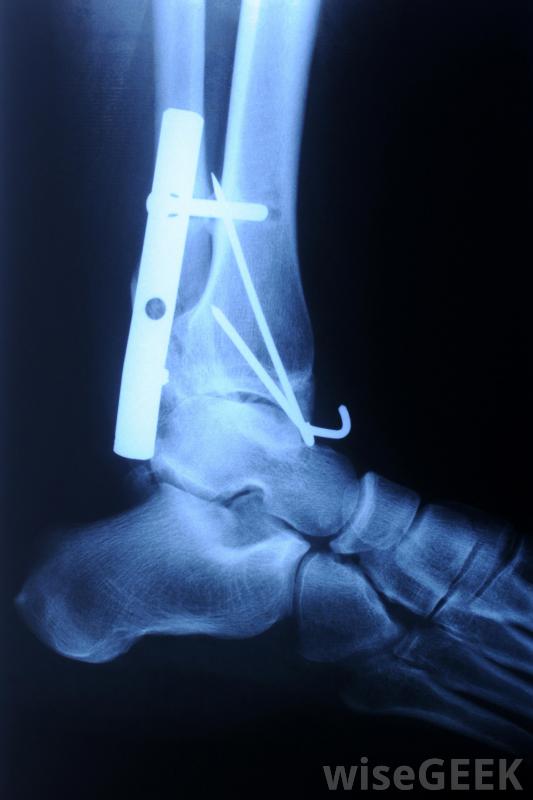

膜内骨化是骨骼愈合的过程。如果脚跟受伤更严重,跟骨骨折的各个部分相互移动,骨头的各个部分通常必须固定在一起。在某些情况下,一种被称为闭合复位的手术可以在全身麻醉下进行。在这里,脚被从外部操纵,将断开的骨头移回原位,这样就不需要把脚完全打开特殊的手术器械是通过脚部的小切口引入的,用来插入固定针和固定线。一种被称为荧光镜的X光片被用来向外科医生显示发生了什么。对于更复杂的跟骨骨折,可以使用所谓的切开复位术。这包括手术来打开在用金属钉和钢板将骨折固定在一起之前,先用脚把骨折暴露出来。这些更复杂的骨折包括影响脚跟和腿之间关节的骨折,如果跟骨骨折导致跟关节严重损伤,关节可能需要用特殊的胶水或螺丝钉固定在一起。

更复杂的跟骨骨折需要手术切开足部,暴露骨折,然后用销钉和钢板固定。